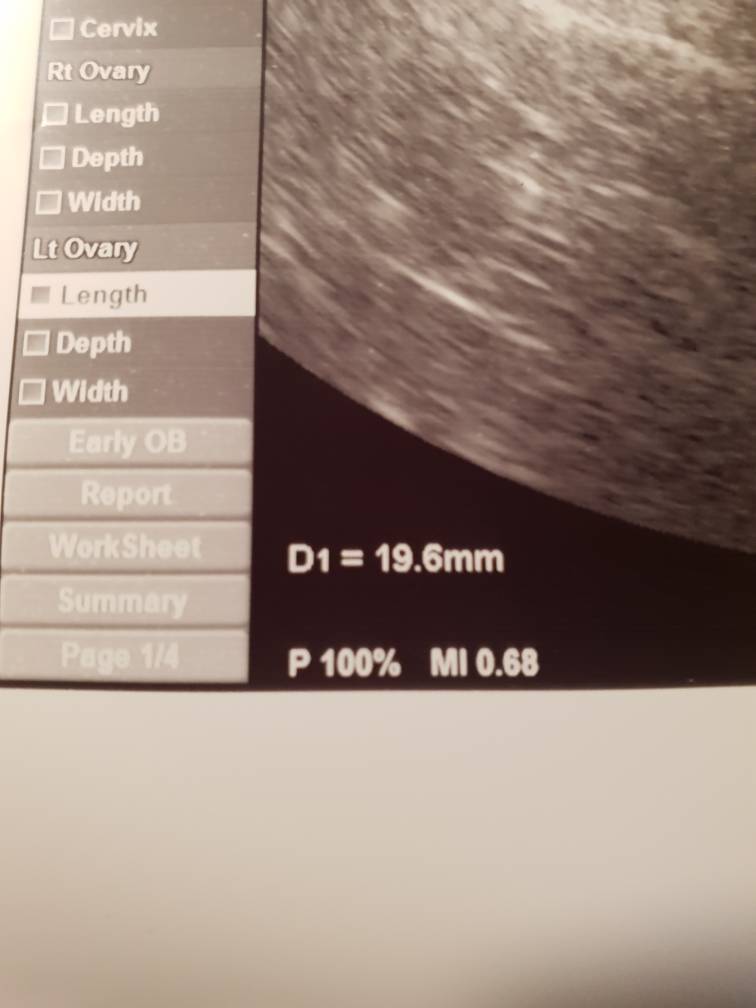

[emoji173]gratulacje [emoji16]Witam [emoji2] U mnie się już sytuacja rozjasnila.. byłam rano na beciewynik 61, więc to na pewno ciąża